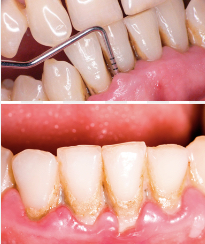

Hygiene and Periodontics

Daily hygiene as a basic element for oral wellbeing requires the addition of periodic oral cleaning sessions in the clinic (tartrectomies) and on many occasions it is necessary to go further when detecting periodontitis and periodontal disease with bone and gum loss. Early diagnosis is key to control these processes. And let us not forget its proven relationship with heart disease.